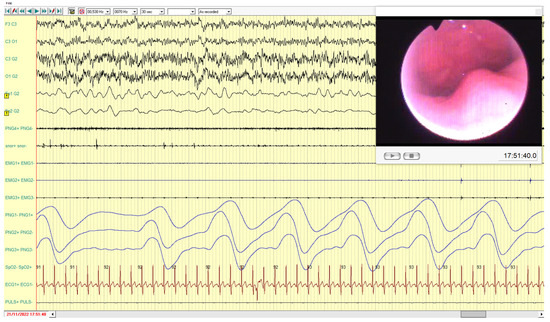

Similarly, for the male patient, results recorded were better with the fork advancement (Figure 8 and Figure 9).

Figure 9. In this frame, the immediate improvement effect on all respiratory parameters with normal saturation values during the mandibular advancement with the fork in place is shown. In addition, masseter muscles are completely suppressed.